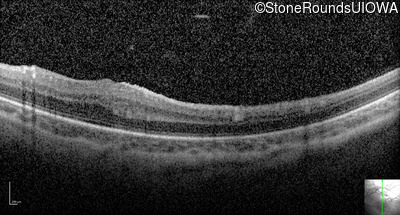

Optical Coherence Tomography - Left - 20/80

Exemplar / OCT Stack